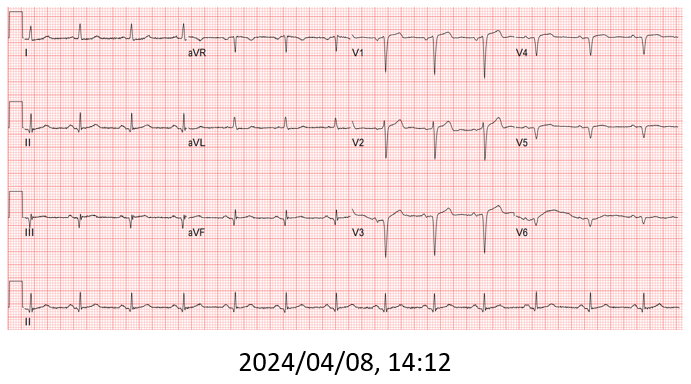

The patient received primary percutaneous coronary intervention (PCI) with balloon angioplasty (POBA) and a drug-eluted stent (DES) for middle LAD. Three days later he underwent staged PCI for RCA. After wire externalization via rendezvous technique, the patient developed acute angina, diaphoresis, and hypotension. Angiogram found a de-novo LAD lesion just distal to the stent.

During the staged PCI, antegrade approach with escalating guidewires ended up in subintimal space; retrograde approach from the first LAD-septal branch failed because there was difficulty crossing the existing mid-LAD stent. Further attempts from the third septal branch successfully reached the distal cap of the CTO via proximal descending artery, finally entering the antegrade guide extension catheter by rendezvous technique. After wire externalization and POBA for RCA, the patient became agitated from acute angina, diaphoresis and hypotension. Angiogram of LAD found an acute de novo LAD lesion adjacent to the distal stent edge, leaving only TIMI-1 flow. We stopped the RCA procedure and wired LAD, performed POBA at the de novo LAD lesion and restored coronary blood flow. Then we continued PCI of RCA with POBA followed by the deployment of two DES. Final angiogram showed adequate stent expansion and TIMI-3 flow in RCA. The patient was discharged with no further complications. Follow-up echocardiogram three months later showed improved wall motion and ejection fraction, indicating good myocardial recovery.